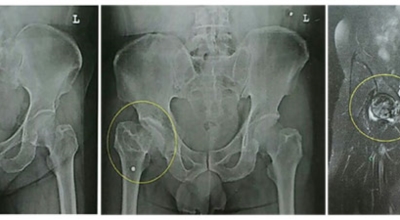

각별히 젊은 남성분들에게 잘 발생하며 엉덩이와 골반 주위에 뻐근한 통증이 동반되며 정상적인 보행이 되지 않고 절뚝거리는 증상이 나타난다면 대퇴골두 무혈성 괴사일 가능성이 있습니다. 이 증상은 괴사 부위의 골절이 발생되어 고관절 훼손으로 이어지면 생기는 증상으로 아직까지 정확한 원인은 규명하기 힘드나 과음이나 고지혈증, 스테로이드 과남용이 영향을 줄 수 있답니다.